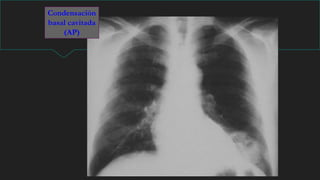

NEUMONIA

Signos Radiológicos:

 Condensación

 Broncograma aereo.

Broncograma

aéreo

NEUMONIA LOBULO MEDIO

DERECHO

Condensación basal izquierda retrocardíaca

Signos radiológicos principales

Absceso

Condensación

basal cavitada

(AP)

TBC: Neumonía

cavitada